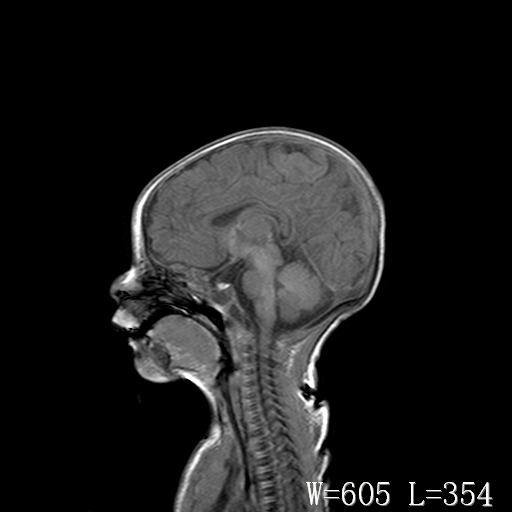

男,4天,发复抽搐1天。

脑干形态欠规则,信号增高,不知怎么解释?

脑干背侧面t1高信号是,新生儿正常已经髓鞘化好的部位